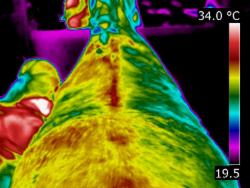

| MUSCLE INJURY | A very valuable use of thermography is in detecting muscle injury. It locates the area of inflammation associated with a muscle or muscle group. It can also show an area of atrophy before it becomes apparent clinically. Atrophy is seen as an area of consistent decrease in circulation when compared to the opposite side. Thermography allows us to see the specific location of strained or torn muscles. It can also help to assess the effects that have been placed on the musculo-skeletal system after extreme exertion and the extent of damage, or secondary damage, after a fall or accident. | | |

| | | When scanning initially, images of the whole horse must be assessed. If a muscle or muscle group shows a raised thermal pattern is the muscle damaged and inflamed or do these muscles simply have increased blood flow because they are working harder to compensate for injury or damage elsewhere? Only a well-trained, experienced thermographer is able to interpret the images.

When inflammation occurs in heavily muscled areas an intense thermal pattern will be evident over the affected area. If oedema and swelling occur over the strained muscle area, the surface temperature may actually become cooler due to subcutaneous fluid accumulation. Both types of images indicate an injury has occurred and careful observations are necessary to detect these differences.